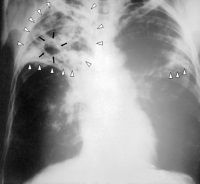

Régies: Tüdőbaj, gümőkór; baktérium okozta fertőző betegség, amely leggyakrabban a tüdőt támadja meg, de megtámadhatja a központi idegrendszert agyhártyagyulladást okozva, illetve a nyirokrendszert és a keringési rendszert is.

A férfi hektikát kapott, ezért a kórházban antibiotikummal kezelik. A tüdőszűrés azért hasznos, mert korán fel lehet ismerni a hektikát, ami így könnyebben kezelhető.